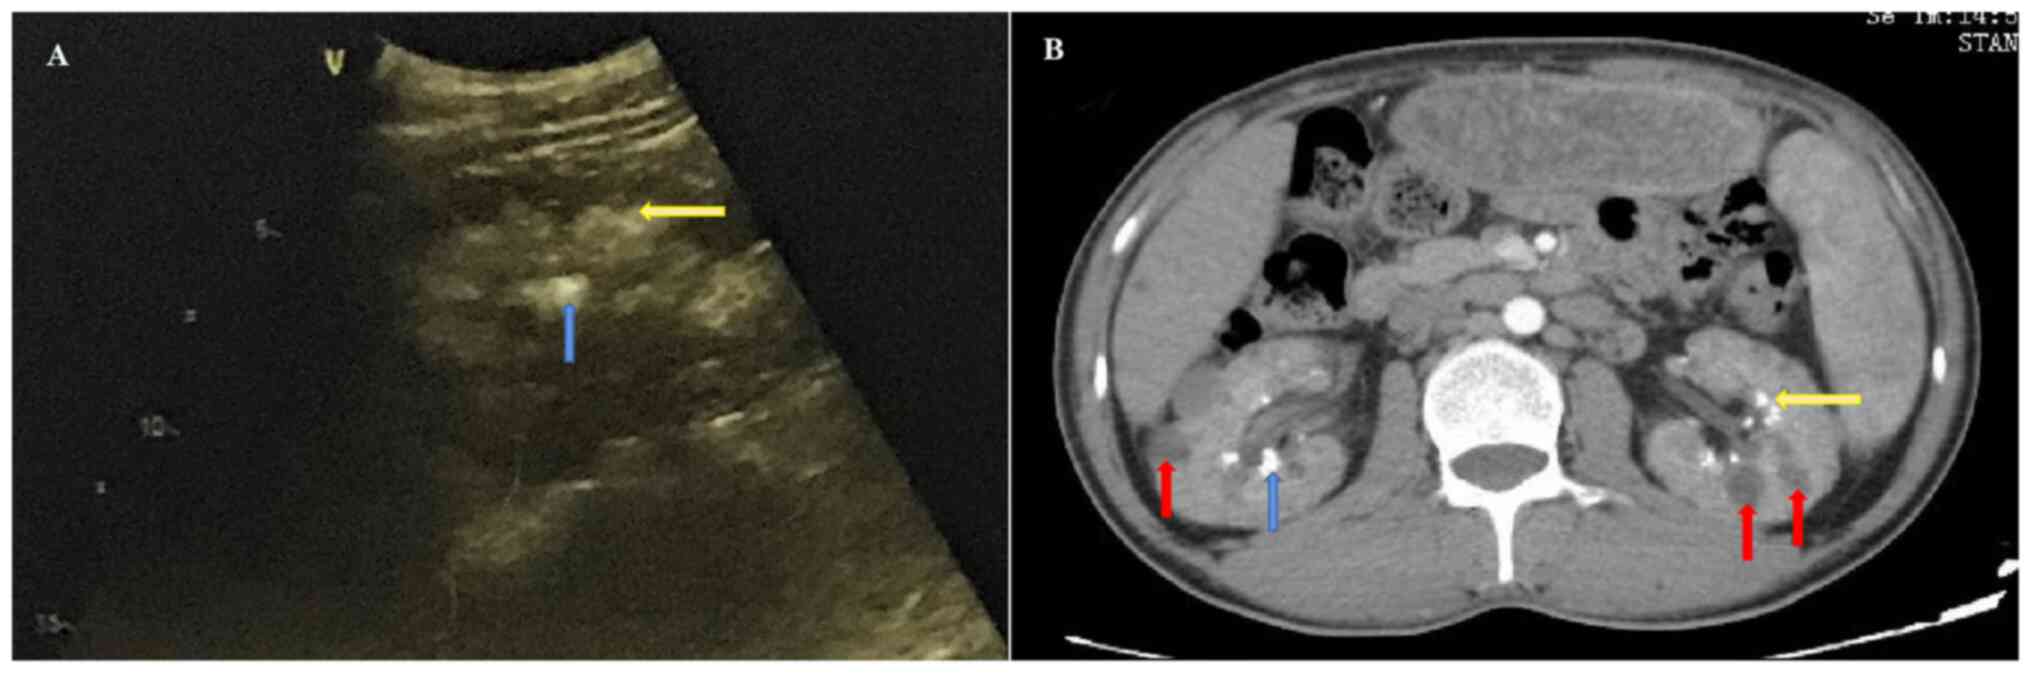

Deep lymph node enlargement and renal failure caused by hypercalcemia‑associated sarcoidosis: A case report

Sarcoidosis is a rare disease that severely affects the lungs and superficial lymph nodes. In addition, this disease can also affect the skin, eyes and kidneys to varying degrees. The present report described a 32‑year‑old male patient who was admitted to Renmin Hospital of Wuhan University (Wuhan, China) due to joint pain in the extremities. He was diagnosed with uncorrectable hypercalcemia. A lymph node biopsy revealed the hypercalcemia to be associated with sarcoidosis, with the patient also demonstrating renal failure and lymph node enlargement. Administration of glucocorticoids provided benefits in terms of both primary and recurrent sarcoidosis, which also improved and preserved renal function. After being prescribed with oral prednisone treatment, blood calcium levels returned to normal, which indicated markedly improving renal function. However, the discontinuation of glucocorticoids for 2 months resulted in increased serum calcium and creatinine levels, both of which returned to abnormal levels. Overall, the present case report suggests that clinicians should actively perform sarcoidosis treatment in clinical practice to overcome any unexpected results associated with organ damage.

Figure 1

Figure 2